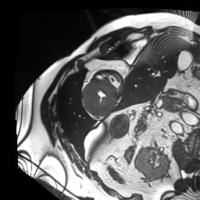

In our semi-supervised segmentation model, the CycleGAN is instead used to map images to their corresponding segmentation mask and vice-versa. The first generator (), corresponding to the segmentation network that we want to obtain, learns a mapping from an image to its segmentation labels. The first discriminator () tries to differentiate these generated labels from real segmentation masks. Note that the combination of of is similar to semi-supervised segmentation approach presented in [31]. Conversely, the second generator () learns to map a segmentation mask to its image. In our semi-supervised segmentation setting, this generator is only used to improve training. Likewise, the second discriminator () receives an image as input and predicts whether this image is real or generated. To enforce cycle consistency, generators are trained so that feeding the labels generated by for an image into gives that same image, and passing back to the image generated by for a segmentation mask gives that same mask. Figure 2 shows examples of images, ground truth labels, generated images and generated labels obtained for the three datasets used in our experiments.

![]() |

| Image | Ground truth labels | Generated image | Generated labels |